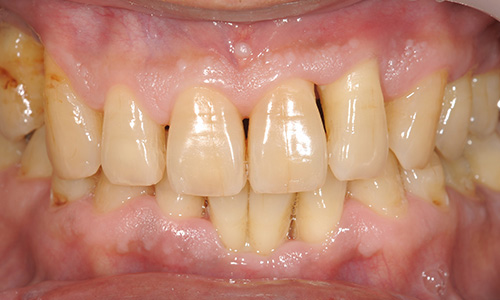

写真の口腔内では部分的に歯ぐきが大きく下がっており、歯根が露出しているため歯が長くみえます。 歯の動揺が大きく、硬いものが咬みにくくなります。たびたび歯ぐきが化膿して腫れるようになります。 口臭が強くなり、起床時には口の中がネバネバした感じになります。